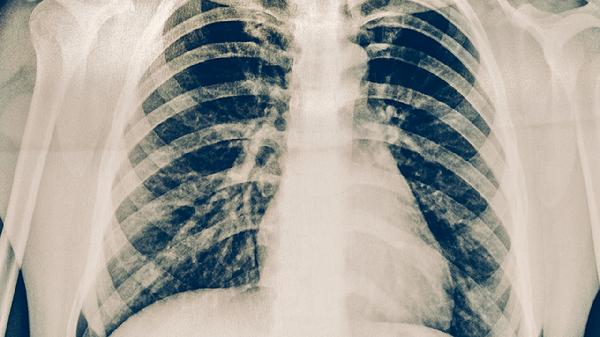

皮肤结核通常会出现红斑、小结节或者溃疡等皮肤病变,常见的类型包括寻常狼疮和疣状结核等。肺结核则会表现出咳嗽、咳血、低烧、夜间盗汗等呼吸系统相关症状,胸部影像检查可见肺部有实质性病变。

诊断皮肤结核需要对皮肤病变进行组织病理学检查,同时结合抗酸染色或PCR检测来确认。而肺结核的诊断则依靠痰液涂片找抗酸杆菌、痰培养、胸部CT等手段,必要时还需做支气管镜检查。